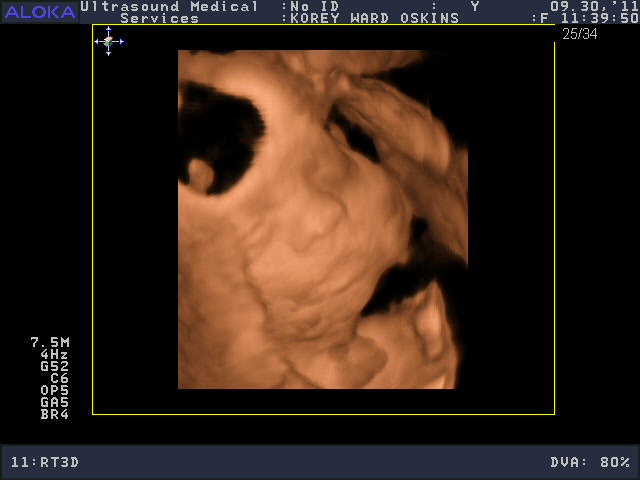

He was a very stubborn baby, so it was really kind of nerve-wracking at first thinking we might not get a single good picture. His face was squished up against the placenta and he wouldn’t budge. You’ll see that in the pictures below; it looks like an enveloping cloud or a scallop shell. Finally he moved a bit and we got some glimpses of his face. We saw him make some facial expressions, wiggle his fingers, and move his mouth around. We were curious to see whose nose he would have, and in some pictures, it looks like he has Josh’s, in others, mine.

So who do you think he looks like?

He is sooooo cute! Personally, I think he looks like ME.